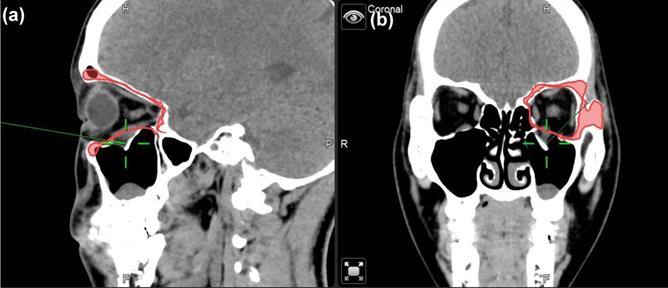

Navigator assisted mirroring tool

To minimize the risk of optic nerve injury and variability of clinical outcomes, navigator assisted mirroring tool was used. Mirroring software from the Brainlab navigator system provided precise recreation of orbital wall symmetry before operation. Contouring of unaffected side of the orbital framework was recognized on CT coronal and axial projections. The mirroring tool of the software copied the outline of unaffected orbital walls. Mirroring and superimposed the object to the affected side to simulate the ideal orbital wall position (Figure 1). Plastic surgeons can plan out surgical procedures based on the superimposed images accordingly.

Figure 1

Case 1 30 y/o female patient with left side orbital floor blow out a fracture. Illustration of mirroring and superimposed the unaffected side (right side) object on the affected side (left side) by Brainlab® navigator software tool. The red line indicated the outline of the mirrored object. (a) Sagittal view of preoperative CT image. Greenline pointed at the fractured left orbital floor. (b) coronal view of preoperative CT image. Greenline pointed at the affected left orbital floor.